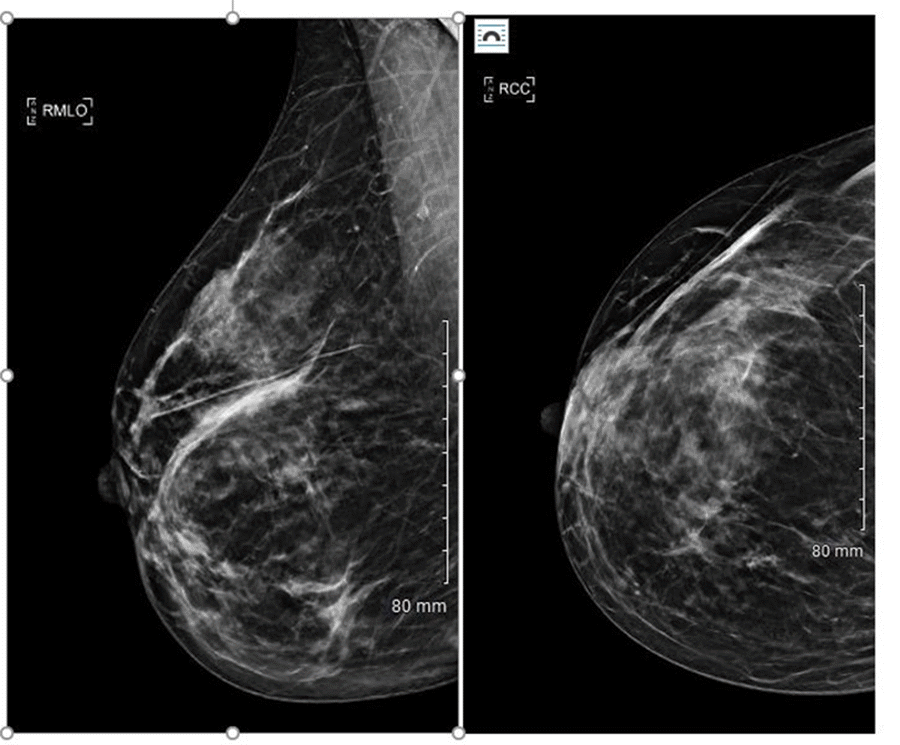

The patient was discharged home on oral clindamycin 300 mg twice daily for ten days, and upon follow-up, there was good granulation tissue present. However, the patient was readmitted to the hospital after having increased swelling and pain over her right lateral breast with obvious firmness. Ultrasound of the breast at this time showed a large area of diffuse heterogeneous echogenicity seen with areas of low echogenicity. The area measured up to 5.3 cm × 2.9 cm × 5.6 cm, but no discrete fluid collection or abscess was appreciated. Infectious disease was consulted, and an extensive work-up for granulomatous mastitis was performed with a mammogram and repeat biopsy as outpatient. (Figure 3)

Figure 3. Mammogram RCC. Published With Permission

Right breast mammogram showing moderately extensive postoperative distortion in outer aspect of right breast. No asymmetric skin thickening. No dominant mass or suspicious calcifications. BIRADS 2-benign.